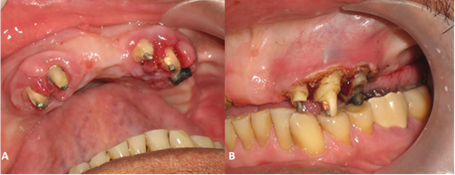

Caso clínico 4

Paciente de sexo masculino de 59 años de edad, con agrandamiento gingival en maxilar superior, a nivel de los órganos dentarios pilares para una prótesis total (Figura 4). Refirió tener antecedente de hipertensión arterial hace 9 años en tratamiento con nifedipino 10mg/8 horas, aproximadamente hace 6 años. Al examen clínico se observó aumento del volumen de la encía marginal y papilar, de aspecto lobulado, y de color rosa pálido a nivel de OD# 12, 13, 22, 23, 24; excepto en encía papilar distal de OD# 12, la cual se encuentra eritematosa y edematizada. Se observan OD# 12 13, 22, 23, 24 previamente tallados y con presencia de núcleos colados (Figura 4A). El procedimiento quirúrgico se realizó sin complicaciones (Figura 4B).